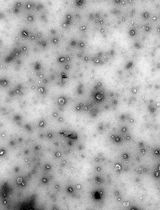

To this end, we developed a two-component system of dibenzocyclooctyne-functionalized multiarm polymers and nanoparticles with azide and activated-platelet-binding moieties, which leverages the increased accumulation of nanoparticles at the injury [8] to achieve crosslinking above a critical concentration, thereby mimicking the presence of fibrin at the wound site. This platform was demonstrated to result in significantly greater platelet recruitment in both normal and hemodiluted systems, increased resistance to fibrinolysis, and prolonged survival in a mouse liver resection model when compared to targeted nanoparticle-only controls.